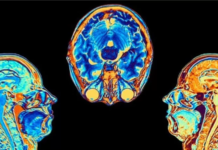

Covid: el estudio que muestra cómo cambia el cerebro tras una infección por coronavirus,...

Rebecca Morelle Contagiarse de covid-19 puede provocar cambios en el cerebro, según indicó un estudio publicado en la revista Nature. Los investigadores hallaron diferencias significativas en las...